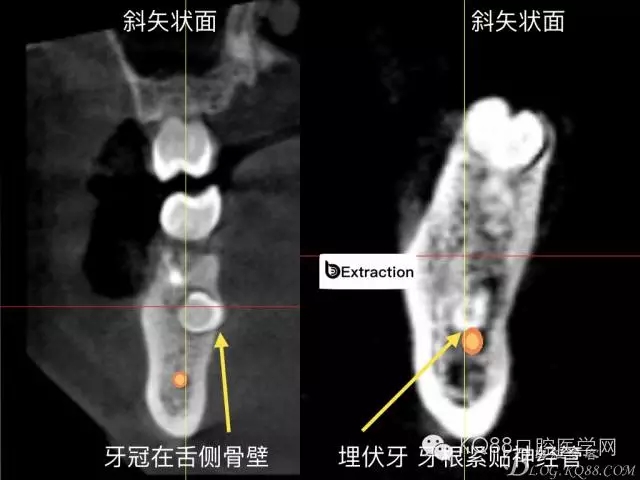

精準拔除術(shù): 下頜高風險埋伏牙